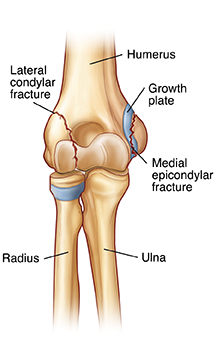

| Lateral condylar fracture and medial epicondylar fracture. |